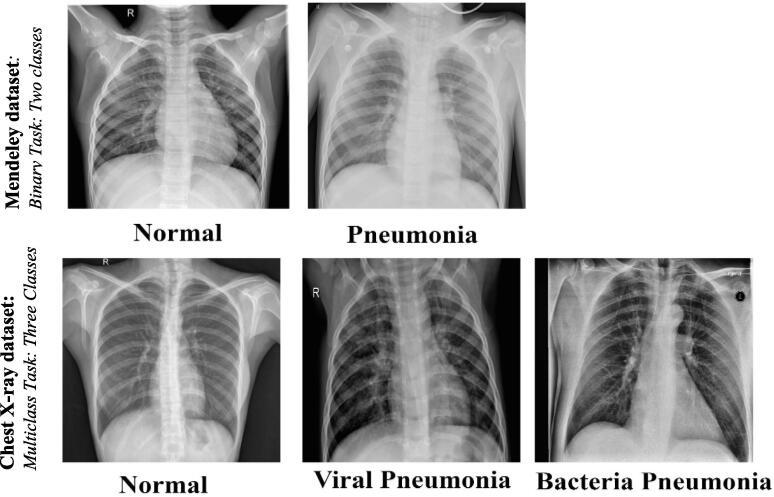

Pneumonia is a microorganism infection that causes chronic inflammation of the human lung cells. Chest X-ray imaging is the most well-known screening approach used for detecting pneumonia in the early stages. While chest-Xray images are mostly blurry with low illumination, a strong feature extraction approach is required for promising identification performance.

The proposed hybrid workflow is developed by fusing the capabilities of both ensemble convolutional networks and the Transformer Encoder mechanism. The ensemble learning backbone is used to extract strong features from the raw input X-ray images in two different scenarios: ensemble A (i.e., DenseNet201, VGG16, and GoogleNet) and ensemble B (i.e., DenseNet201, InceptionResNetV2, and Xception). Whereas, the Transformer Encoder is built based on the self-attention mechanism with multilayer perceptron (MLP) for accurate disease identification. The visual explainable saliency maps are derived to emphasize the crucial predicted regions on the input X-ray images. The end-to-end training process of the proposed deep learning models over all scenarios is performed for binary and multi-class classification scenarios.